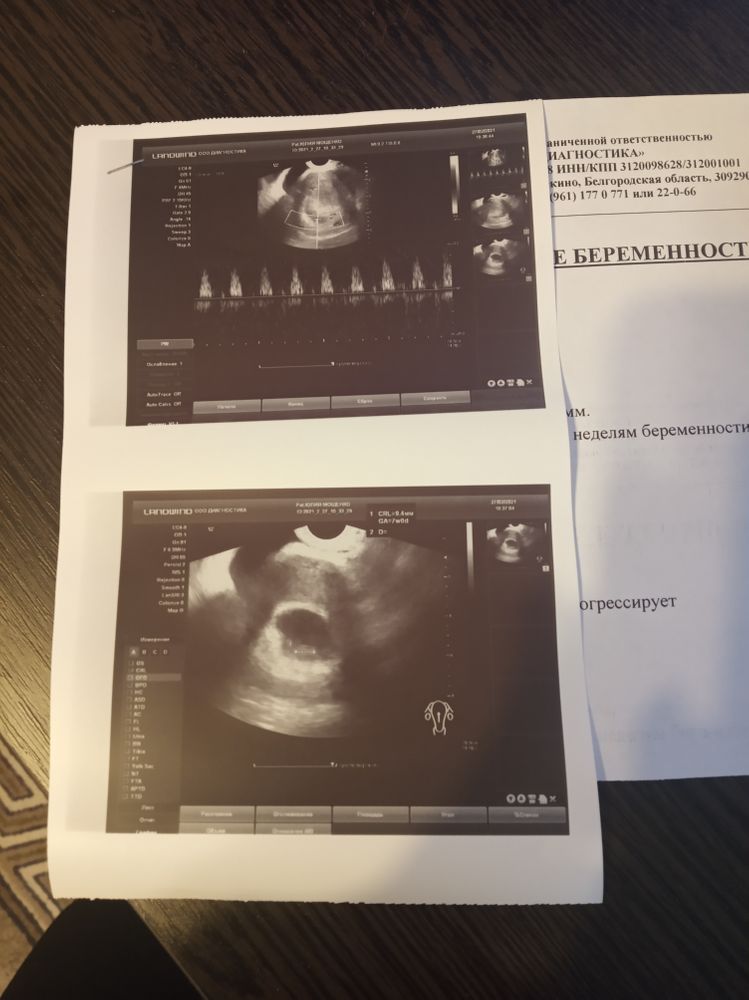

Всё о нашей беременностиДобрый день, девочки везде ставят разный срок,как правильно считать от первого дня м или после переноса? Сегодня услышала сердечко,это норма? Модераторы , исправьте пожалуйста если неправильно выбрала категорию,